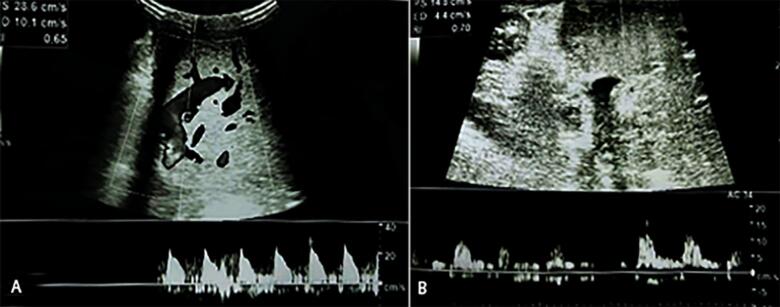

Presentation of case: A 13-month-old infant with biliary atresia post-Kasai procedure underwent living donor liver transplantation. On postoperative day 9, Doppler ultrasound detected signs of impending hepatic artery thrombosis, which was confirmed by computed tomography angiography. The patient was treated with intravenous alteplase at a dose of 0.3 mg/kg/h. After 3.5 hours of infusion, Doppler ultrasound showed improved hepatic artery flow. The infusion was stopped early due to intra-abdominal bleeding, which was managed conservatively. The patient stabilized without surgical intervention and was discharged on postoperative day 32 with stable hepatic artery flow. At six-month follow-up, the hepatic artery remained patent, and the patient was clinically stable.